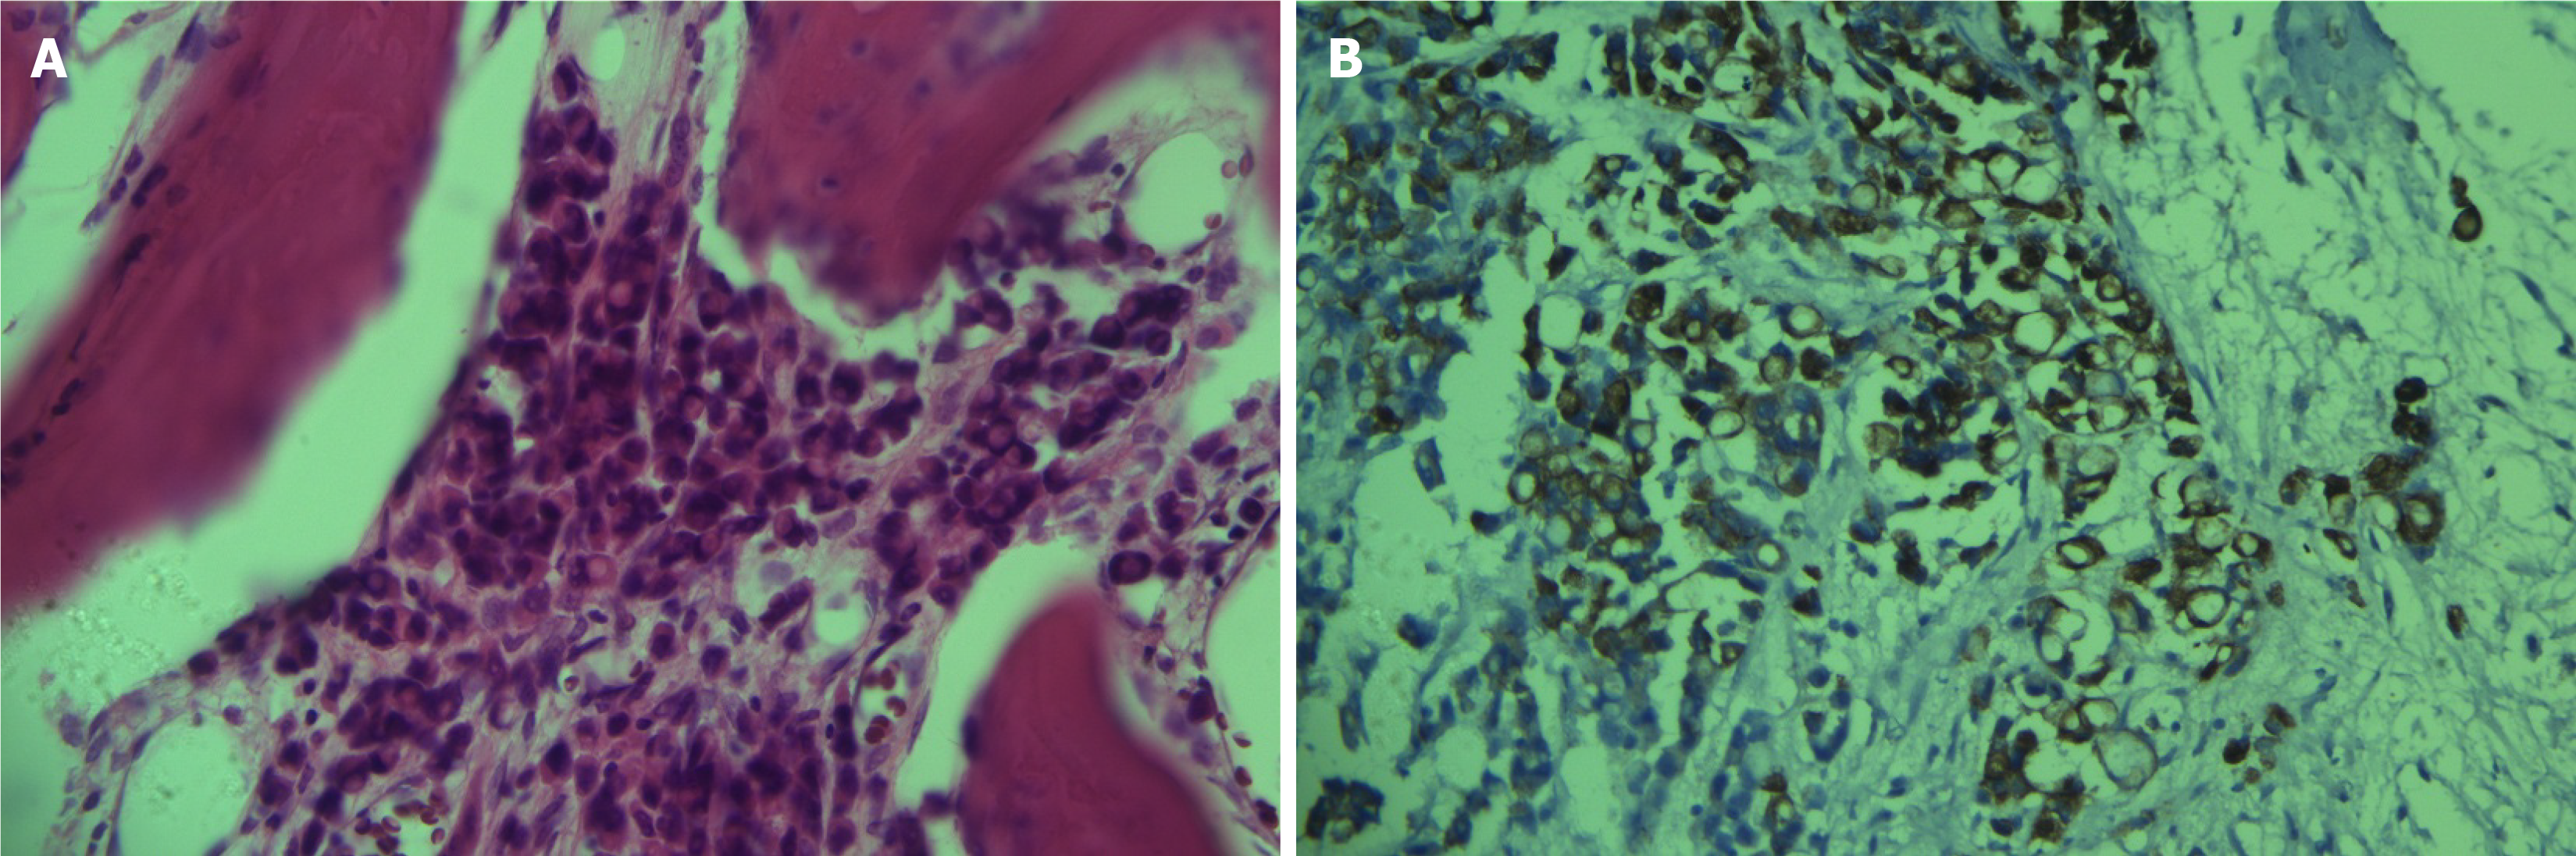

Figure 2 Hematoxylin and eosin staining and immunohistochemical results of the patient’s bone tissue.

A: Pathology showed metastatic adenocarcinoma (400 ×); B: Immunochemistry of bone tissue showed positive staining for cytokeratin 7 (400 ×).